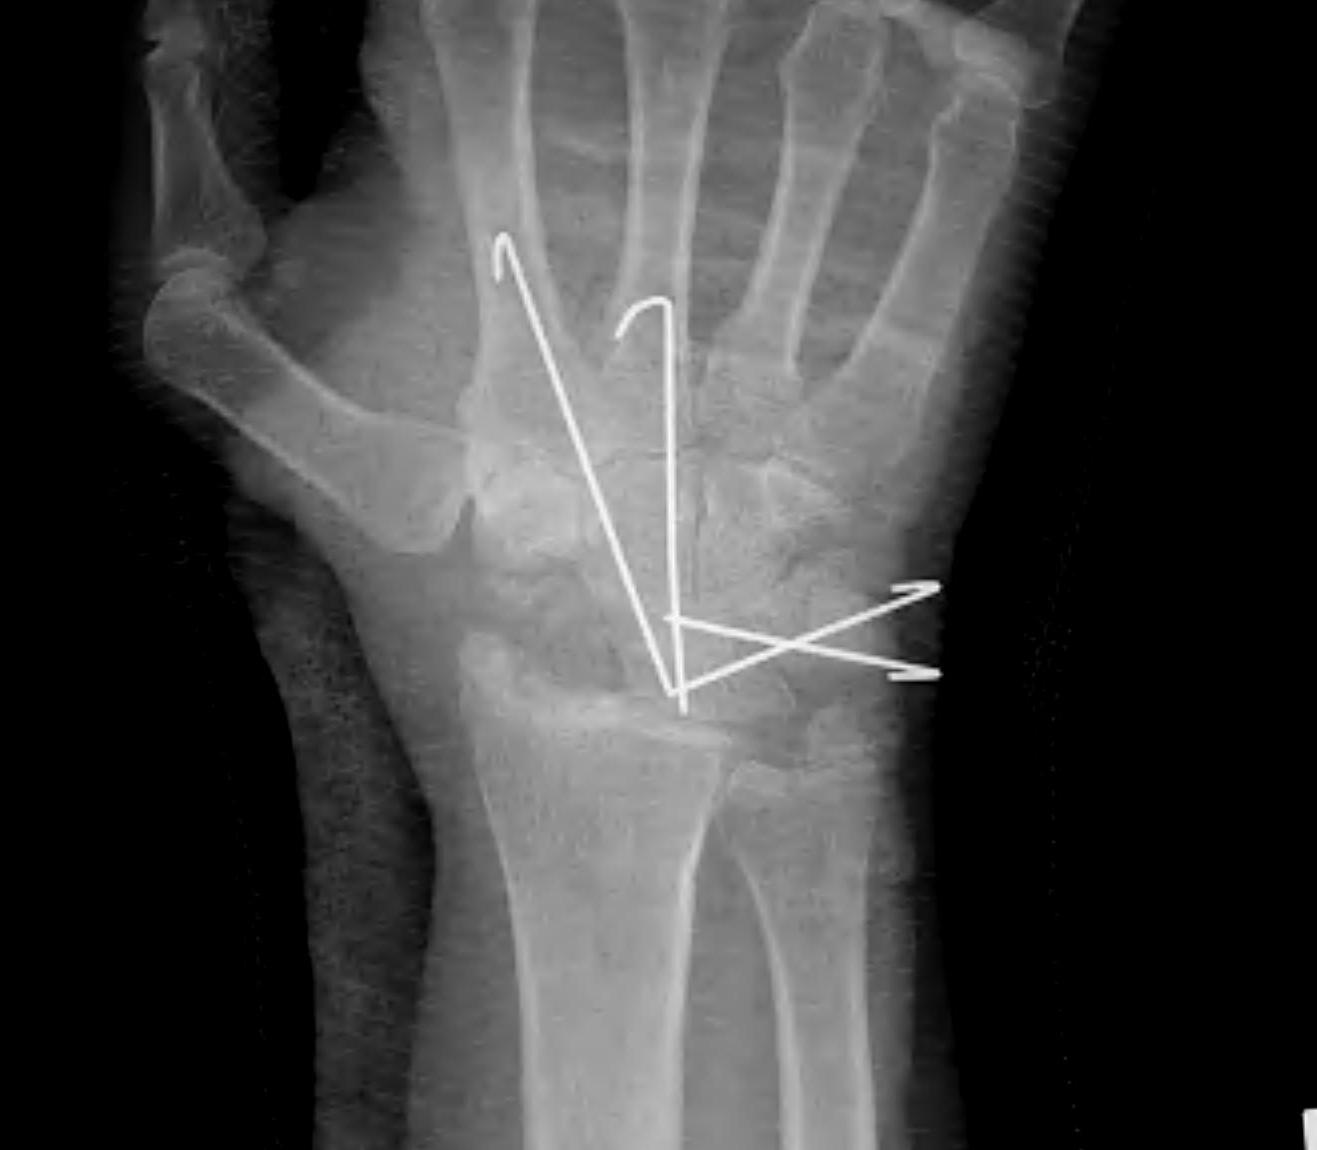

5. Scaphoidectomy & 4 corner fusion

Definition

Scaphoid non union advanced collapse